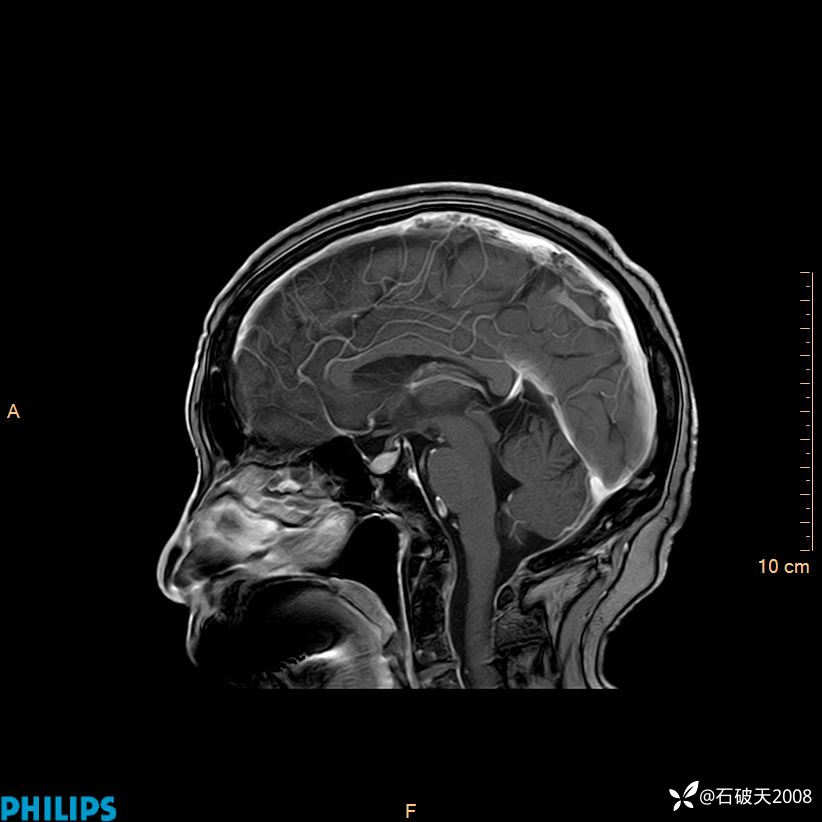

增强矢状位